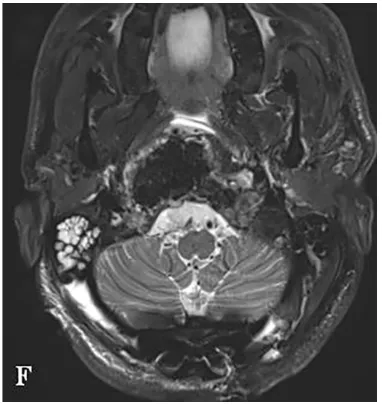

术前MRI显示肿瘤呈浸润性生长,向双侧后外侧扩展,右侧受累尤为严重。肿瘤侵袭至椎前间隙、下斜坡、双侧枕骨髁、第一颈椎C1前弓及C2齿状突。

为尽可能安全切除肿瘤,福教授制定综合治疗方案,术中除使用"筷子技术"外,还采用"双镜联合"技术。首先在显微镜下暴露肿瘤并进行瘤内减压,再使用神经内镜辅助探查,借助"筷子技术"切除对侧肿瘤。最后采用Roy-Camille技术进行枕颈融合术,为后续质子治疗创造无金属的定位和治疗通道。

术后MRI显示肿瘤完全切除,脑干和延髓的占位性压迫解除。